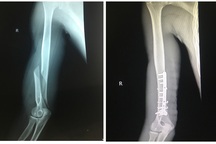

Hình ảnh phim chụp X-quang cho thấy xương cánh tay bị gãy (Ảnh: Bác sĩ cung cấp).

"Gãy xương trong khi đang vật tay thường do cơ chế xoắn vặn nên ổ gãy thường là dạng chéo vát, có thể có mảnh rời. Người tham gia thường dùng một lực rất lớn lên cánh tay khi khuỷu cố định trong tư thế gấp, dẫn tới một lực rất lớn dồn vào vùng 1/3 dưới xương cánh tay là vùng chuyển tiếp giữa thiết diện tròn và tam giác của thân xương, nguy cơ gãy xương rất cao.